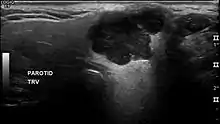

The diagnosis of salivary gland tumors utilize both tissue sampling and radiographic studies. Tissue sampling procedures include fine needle aspiration (FNA) and core needle biopsy (bigger needle comparing to FNA). Both of these procedures can be done in an outpatient setting. Diagnostic imaging techniques for salivary gland tumors include ultrasound, computer tomography (CT) and magnetic resonance imaging (MRI).

In terms of imaging studies, ultrasound can determine and characterize superficial parotid tumors. Certain types of salivary gland tumors have certain sonographic characteristics on ultrasound.[6] Ultrasound is also frequently used to guide FNA or core needle biopsy.